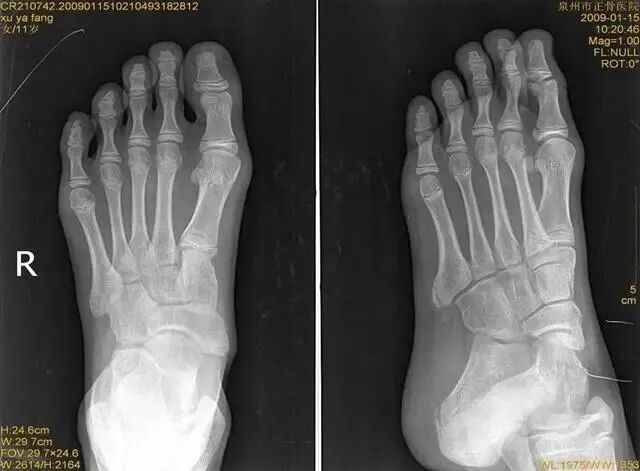

踝关节扭伤

是最常见的踝部损伤之一,据估计,全世界范围内每天每1万人中就有1人踝关节扭伤,扭伤可发生于运动员,也常见于普通人。